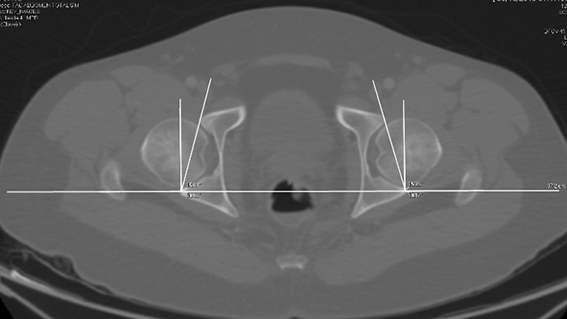

Acetabular anteversion angle was measured by drawing a line in the horizontal plane through the posterior edge of both acetabula, then a second line was made perpendicular to the first one, at the level of the same posterior edge of the acetabulum for each side of the hips. Finally, a third line that runs from the anterior margin of the acetabulum to the posterior margin of the acetabulum was drawn. The acetabular anteversion angle is the measure of the angle between the second and the third lines for each side. (Figure 1)

Figure 1

Figure 1. Acetabular anteversion angle measurement